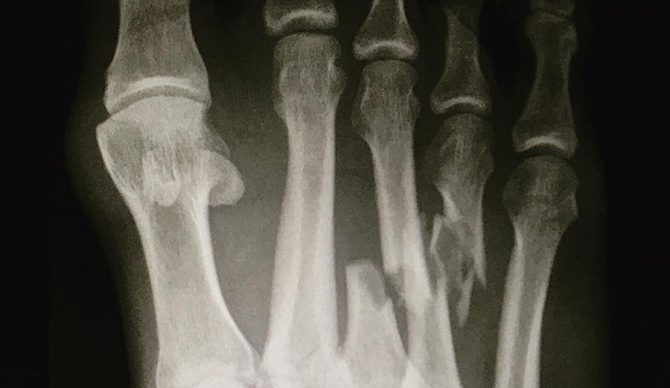

After picking my jaw up off the floor this week, I started processing the severity of what had happened to Kelly Slater’s foot. I couldn’t help but to think well.. this season is probably done. Not to be Debby Downer, but he fully broke and displaced his third and fourth metatarsals on his rear foot. It’s kind of a big deal.

Metatarsals play an important role in gripping, balancing, and assisting the toes with sagittal plane movement. Additionally, some of the metatarsals serve as anchor points for foot and ankle tendons that are critical for surfing. I will say that if there was a silver lining for Slater’s recent injury it’s that he managed to spare his 1st metatarsal, which is critical for walking, pushing off the ground, and certainly crucial for driving the board down the line (if you don’t believe me, check out his first metatarsal area that shows extra bone growth formation, indicative of repetitive use and possible a pretty cool adaptation for his foot). Also, Slater managed to spare his 5th Metatarsal which is an anchoring point for peroneus brevis a critical muscle for everything.

Kelly, if you have to break your metatarsals, this is a pretty eloquent way to pull it off.